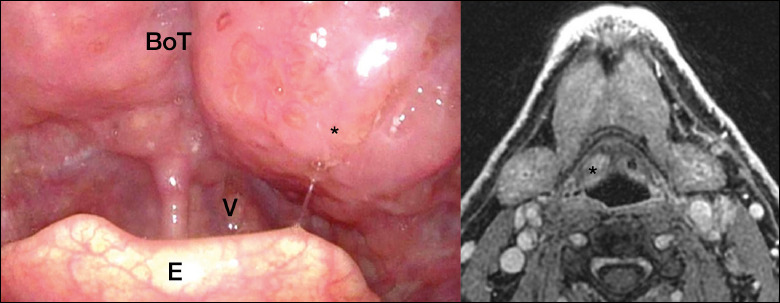

Objectives: Several devices have been developed to improve head and neck surgery. 3D exoscopes provide surgeons a viable alternative to microscopes. We propose our setting for transoral exoscopic oropharyngeal (TOEOS) and transoral exoscopic laryngeal surgery (TOELS).

Results: Among 40 patients undergoing TOELS for glottic and supraglottic tumours, negative superficial and deep margins were achieved in 79.2% and 75% of patients, respectively. The mean operative time was 73.7 ± 35.9 minutes. Fourteen patients were treated by TOEOS and in only one case was re-resection required due to a positive deep margin. The mean operative time for TOEOS was 140.3 ± 82.1 minutes and the average duration of hospitalisation was 10.3 ± 3.8 days.

Conclusions: 3D exoscopes improve visualisation of the surgical site in different environments and allow the use of multiple surgical instruments and lasers, easing transoral surgery. In addition, as the first surgeon's view is shared between the operatory room (OR) staff, the exoscopic setup plays a crucial role in the collaboration between the OR team and for teaching purposes.